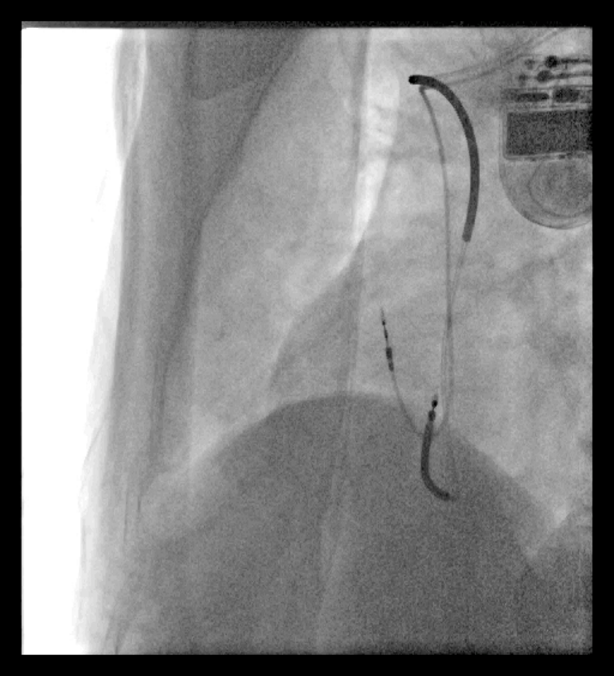

刘师傅的手术进行顺利,医生为刘师傅植入了美敦力ICD, 并在术后程控起搏器参数尽量减少心室起搏。这时候刘师傅的一颗悬着的心才稍微放宽了,本来害怕出院的担忧也逐渐被改变了。

一个月之后,刘师傅来门诊随访。自从安装了ICD,他感觉良好,感觉就像从未发过病一样。在随访问询中,发现刘师傅这一个月中有发生4次FVT事件,好在都被ICD成功捕获,ATP治疗成功,整个过程也就持续几秒钟,刘师傅根本没有察觉到。当医生告诉他这个事件的时候,刘师傅非常惊讶,原来自己以为的岁月静好,是因为有ICD在为他保驾护航,就像身边有一个机警的保镖时刻守护自己,顿时,之前的焦虑也几乎没有了,安全感十足。